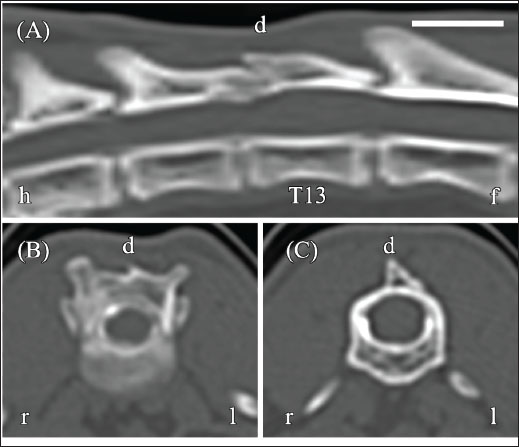

An approximately 7-month-old female Japanese domestic shorthair was referred to Matsuno Pet Clinic with paresis of both pelvic limbs and a history of back trauma since adoption. The cat had previously been treated with antibiotics for trauma, but pelvic limb paresis persisted. Approximately 1 month later (day −118), CT myelography was performed at Akita Komatsu Animal Hospital using a Brivo CT 385 scanner (GE Healthcare, Chicago, IL, USA) (slice thickness, 1.25 mm; reconstruction kernel, BONEPLUS). Iohexol (Omnipaque 240, 240 mg I/ml; GE Healthcare) was administered via lumbar puncture at a dose of 0.5 ml/kg under the guidance of C-arm fluoroscopy (Brivo OEC 785; GE Healthcare). Scans were obtained approximately 5 minutes after the injection. Contrast distribution and the presence or absence of extradural/intradural filling defects were assessed. A bone tissue window (window width, 3000 HU; window level, 500 HU) was used for analysis. These studies revealed spinal cord compression caused by a T13 vertebra fracture and a “teardrop sign” in the contrast column at the same site (Fig. 1A–C). Although no obvious fracture line was observed in T12, spinal cord compression due to dorsal lamina thickening was noted.

Fig. 1. Computed tomography (CT) myelography of the thoracolumbar vertebrae obtained 4 months prior (day−118). (A) Reconstructed sagittal CT myelography shows dorsal compression of the spinal cord (black arrow), a T13 vertebral fracture (white arrow), and teardrop-shaped fluid accumulation (asterisk) at the dorsal aspect of T13. (B) Transverse image at the T12–T13 level demonstrates spinal cord flattening. (C) Transverse image at the T13 level shows fluid accumulation (asterisk) compressing the dorsal spinal cord. Images were acquired using a bone tissue window (window width, 3,000 HU; window level, 500 HU). Orientation markers: h=head, f=foot, r=right, l=left. Scale bar=1 cm.